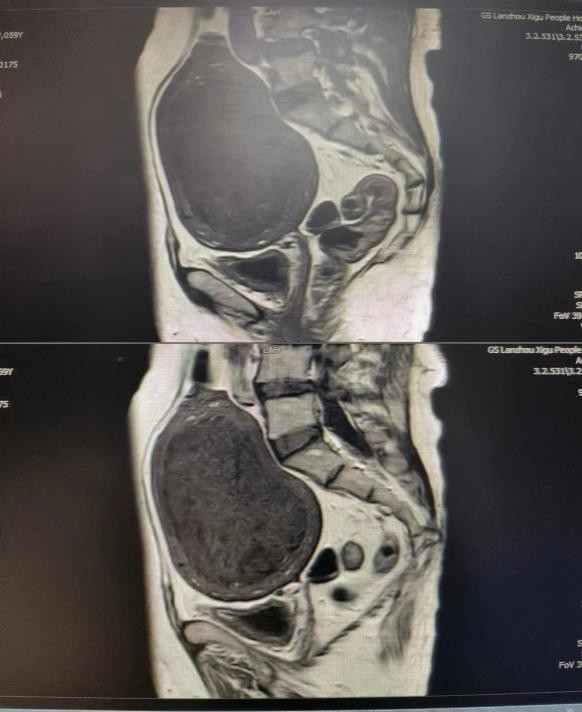

患者59岁,绝经期女性,因自觉腹部膨隆,检查发现巨大子宫肌瘤,遂于妇科住院治疗,入院后查体子宫如孕近5月大小,行盆腔核磁检查,排除恶性可能。积极调控血糖,经术前MDT讨论、充分术前综合评估,因患者体质肥胖、“2型糖尿病”,手术风险增加,难度系数大,与患者及其家属沟通后,制定了最佳的治疗方案,决定行“腹腔镜下全子宫切除术”。手术过程顺利、恢复快,术后5天康复出院。